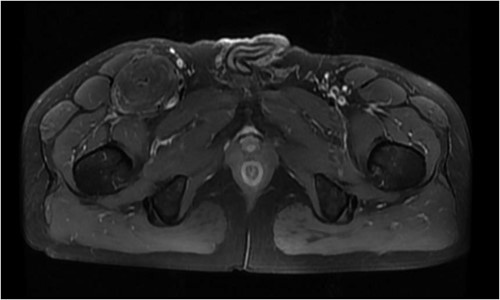

The patient was admitted to the hospital due to the discovery of an inguinal mass that had been present for 1 year. The patient initially noticed swelling in the groin area a year ago. Over time, it gradually increased in size and caused localized discomfort. During the examination, a mass the size of a hen’s egg was felt in the right inguinal region. It had limited mobility and was not tender. No significant abnormalities were found in the motion or sensation of the right lower limb. Ultrasonography showed an isoechoic mass within the muscle tissue of the left inguinal region. Unenhanced and enhanced magnetic resonance imaging (MRI) scans suggested a well-defined intermuscular mass at the root of the right thigh. The mass showed low signal intensity on diffusion-weighted imaging and isointense-to-slightly hyperintense signal post-enhancement (Fig. 1). The patient then underwent excisional biopsy. The excised tissue showed a capsulated, lobulated, soft and greasy mass with a brownish-yellow cut surface. Ultrastructural examination revealed large multivacuolated adipocytes with eccentric nuclei, cytoplasmic acidophilic granules and small lipid droplets. Additionally, abundant blood vessels were present within the stroma. Immunohistochemistry results showed positive staining for S100 protein and negative staining for CD34 (Fig. 2).

Hibernomas are rare adipocytic tumors that primarily affect individuals aged 30–40 years old. They are commonly found in regions rich in brown adipose tissue, such as axillary fossae, necks and interscapular areas. Cases have also been reported in abdominal regions, thighs and buttocks. Hibernomas rarely undergo malignant transformation, with only a minority of cases recurring due to incomplete excision [2]. Clinically, hibernomas present as slow-growing, painless masses. As they grow, they may exert pressure on surrounding tissues, leading to symptoms of vascular and neural compression. Commonly used imaging modalities include ultrasonography, computed tomography (CT), MRI and positron emission tomography combined with CT (PET/CT), with angiographic examination as an auxiliary tool. Ultrasonography reveals well-defined borders and high-echoic lesions. Doppler imaging allows observation of abundant blood flow signals. CT scans without contrast typically show well-circumscribed, lobulated soft tissue masses with density similar to subcutaneous fat, but with slight variation. Detailed examination may reveal linear or curvilinear internal septations. On T1- and T2-weighted MRI images, hibernomas appear isointense or slightly hyperintense. In certain regions, fat-suppressed sequences show high signal intensity. After contrast enhancement, heterogeneous enhancement patterns are commonly observed [3]. However, differentiating hibernomas from liposarcomas remains challenging using CT and MRI.